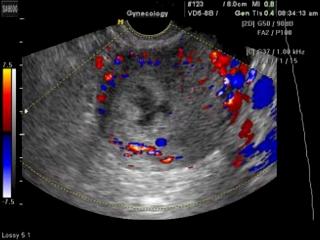

Uterus - subchorionic bleeding, color doppler

SonoAce-8000. Uterus - subchorionic bleeding, color doppler.